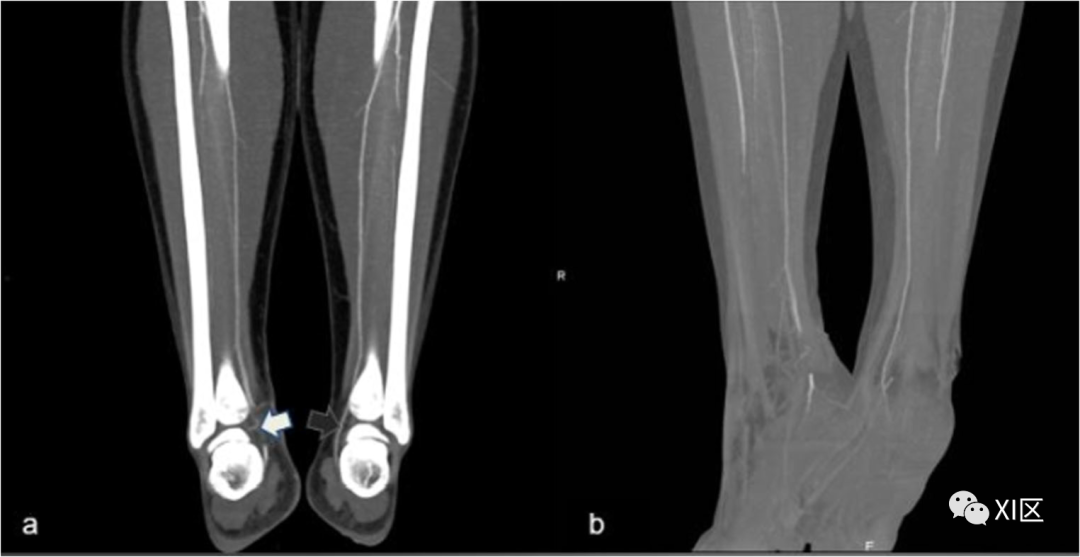

血肿是软组织中的高密度病变;它可能与活动性出血的迹象有关,表现为造影剂外渗(图8)。

图8 腹股沟血肿伴活动性出血。73岁女性,车祸后CTA轴位图像;a 平扫,b 动脉期。在a组,腹股沟处有明显的大血肿;注射造影剂后,出现不规则的血管外增强(箭头)(b),这是持续出血的迹象。右腹股沟前部可见金属碎片

当所有血管壁层都被破坏时,就会发生主动外渗。CTA需要区分持续出血和无活动性出血的血肿。在凝块性血肿中,没有明显的造影剂积聚迹象,而血肿内管腔外造影剂聚集不清或软组织和肌肉浸润则是活动性出血。CTA还可以帮助区分小血管出血(可以保守治疗)和大分支出血(必须手术治疗)。血管横断/闭塞表现为造影剂增强血管腔突然停止/中断,有或无血管远端复发(图9)。